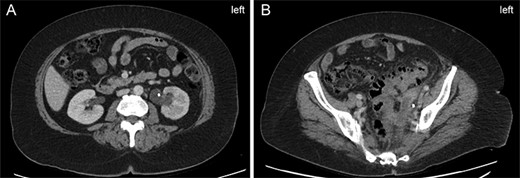

A 61-year-old female presented to emergency with a rapidly worsening soft tissue infection of her left buttock extending to her posterior thigh. Her recent medical history was unusual. Previously healthy and taking no regular medications, she developed a chronic left perineum sinus which was excised 2 years prior to presentation. A CT scan and colonoscopy as part of her workup uncovered asymptomatic sigmoid diverticulosis. A year later she developed a left maxillary sinus mass with a radiographical differential diagnosis including granulomatosis with polyangiitis (final pathology on excision showed only osteomyelitis). Repeat CT scan during this workup now showed new left-sided hydronephrosis overlain with inflammatory changes in keeping with a chronic sigmoid diverticulitis (Fig. 1), despite an otherwise clinically asymptomatic abdomen. Colorectal carcinoma was ruled out by a repeat colonoscopy 8 months prior to presentation. The hydronephrosis was managed by ureteric stenting, and the patient opted for conservative management of her diverticulitis.

Left-sided hydronephrosis 6 months prior to presentation. (A) Left-sided hydronephrosis demonstrated at renal hilum with ureteric stent in place. (B) Demonstration of extensive diverticuli and surrounding inflammatory changes in the same CT scan as Panel A. Uretic stent is again seen.